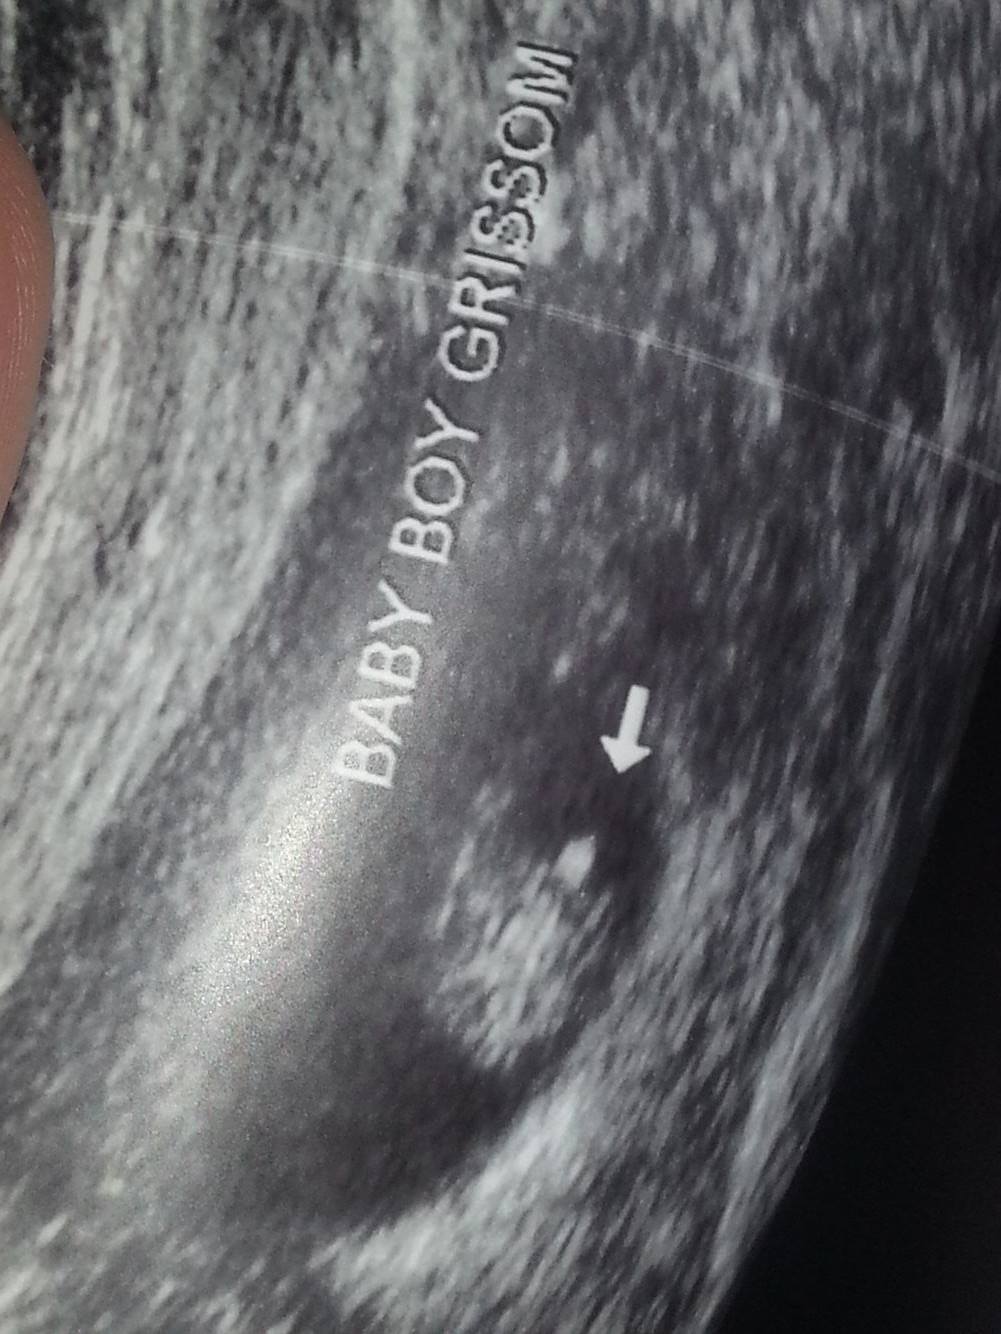

HELPPPP... Have been told: BOY (14wks), BOY (16wks), GIRL(17wks), & GIRL (18wks)

HELPPPP... Have been told: BOY (14wks), BOY (16wks), GIRL(17wks), & GIRL (18wks)!!

Absolutely completely confused & upset. A tech friend who works at our local hospital (so not an OB tech that views gender everyday, but does has experience & has been doing them for years) has been performing ultrasounds for me just out of excitement herself. I've so appreciated being able to watch my baby grow as I am high risk, & it keeps my mind at ease! BUT gender predictions have been a nightmare thus far. My latest just doesnt seem like normal "girl parts" to me. It is protruding far more than what I have seen on my two previous girls. The base of the the "three lines" isnt even attached at the bottom of the baby. Its odd to say the least. But some opinions will be greatly appreciated. My actual OB will be doing a gender u/s next week at 21 weeks so hopefully we will get some clarity. Regardless I feel like I will have a hard time trusting it & getting to bond with my SON or DAUGHTER :( ... hellllpAttachment 31823